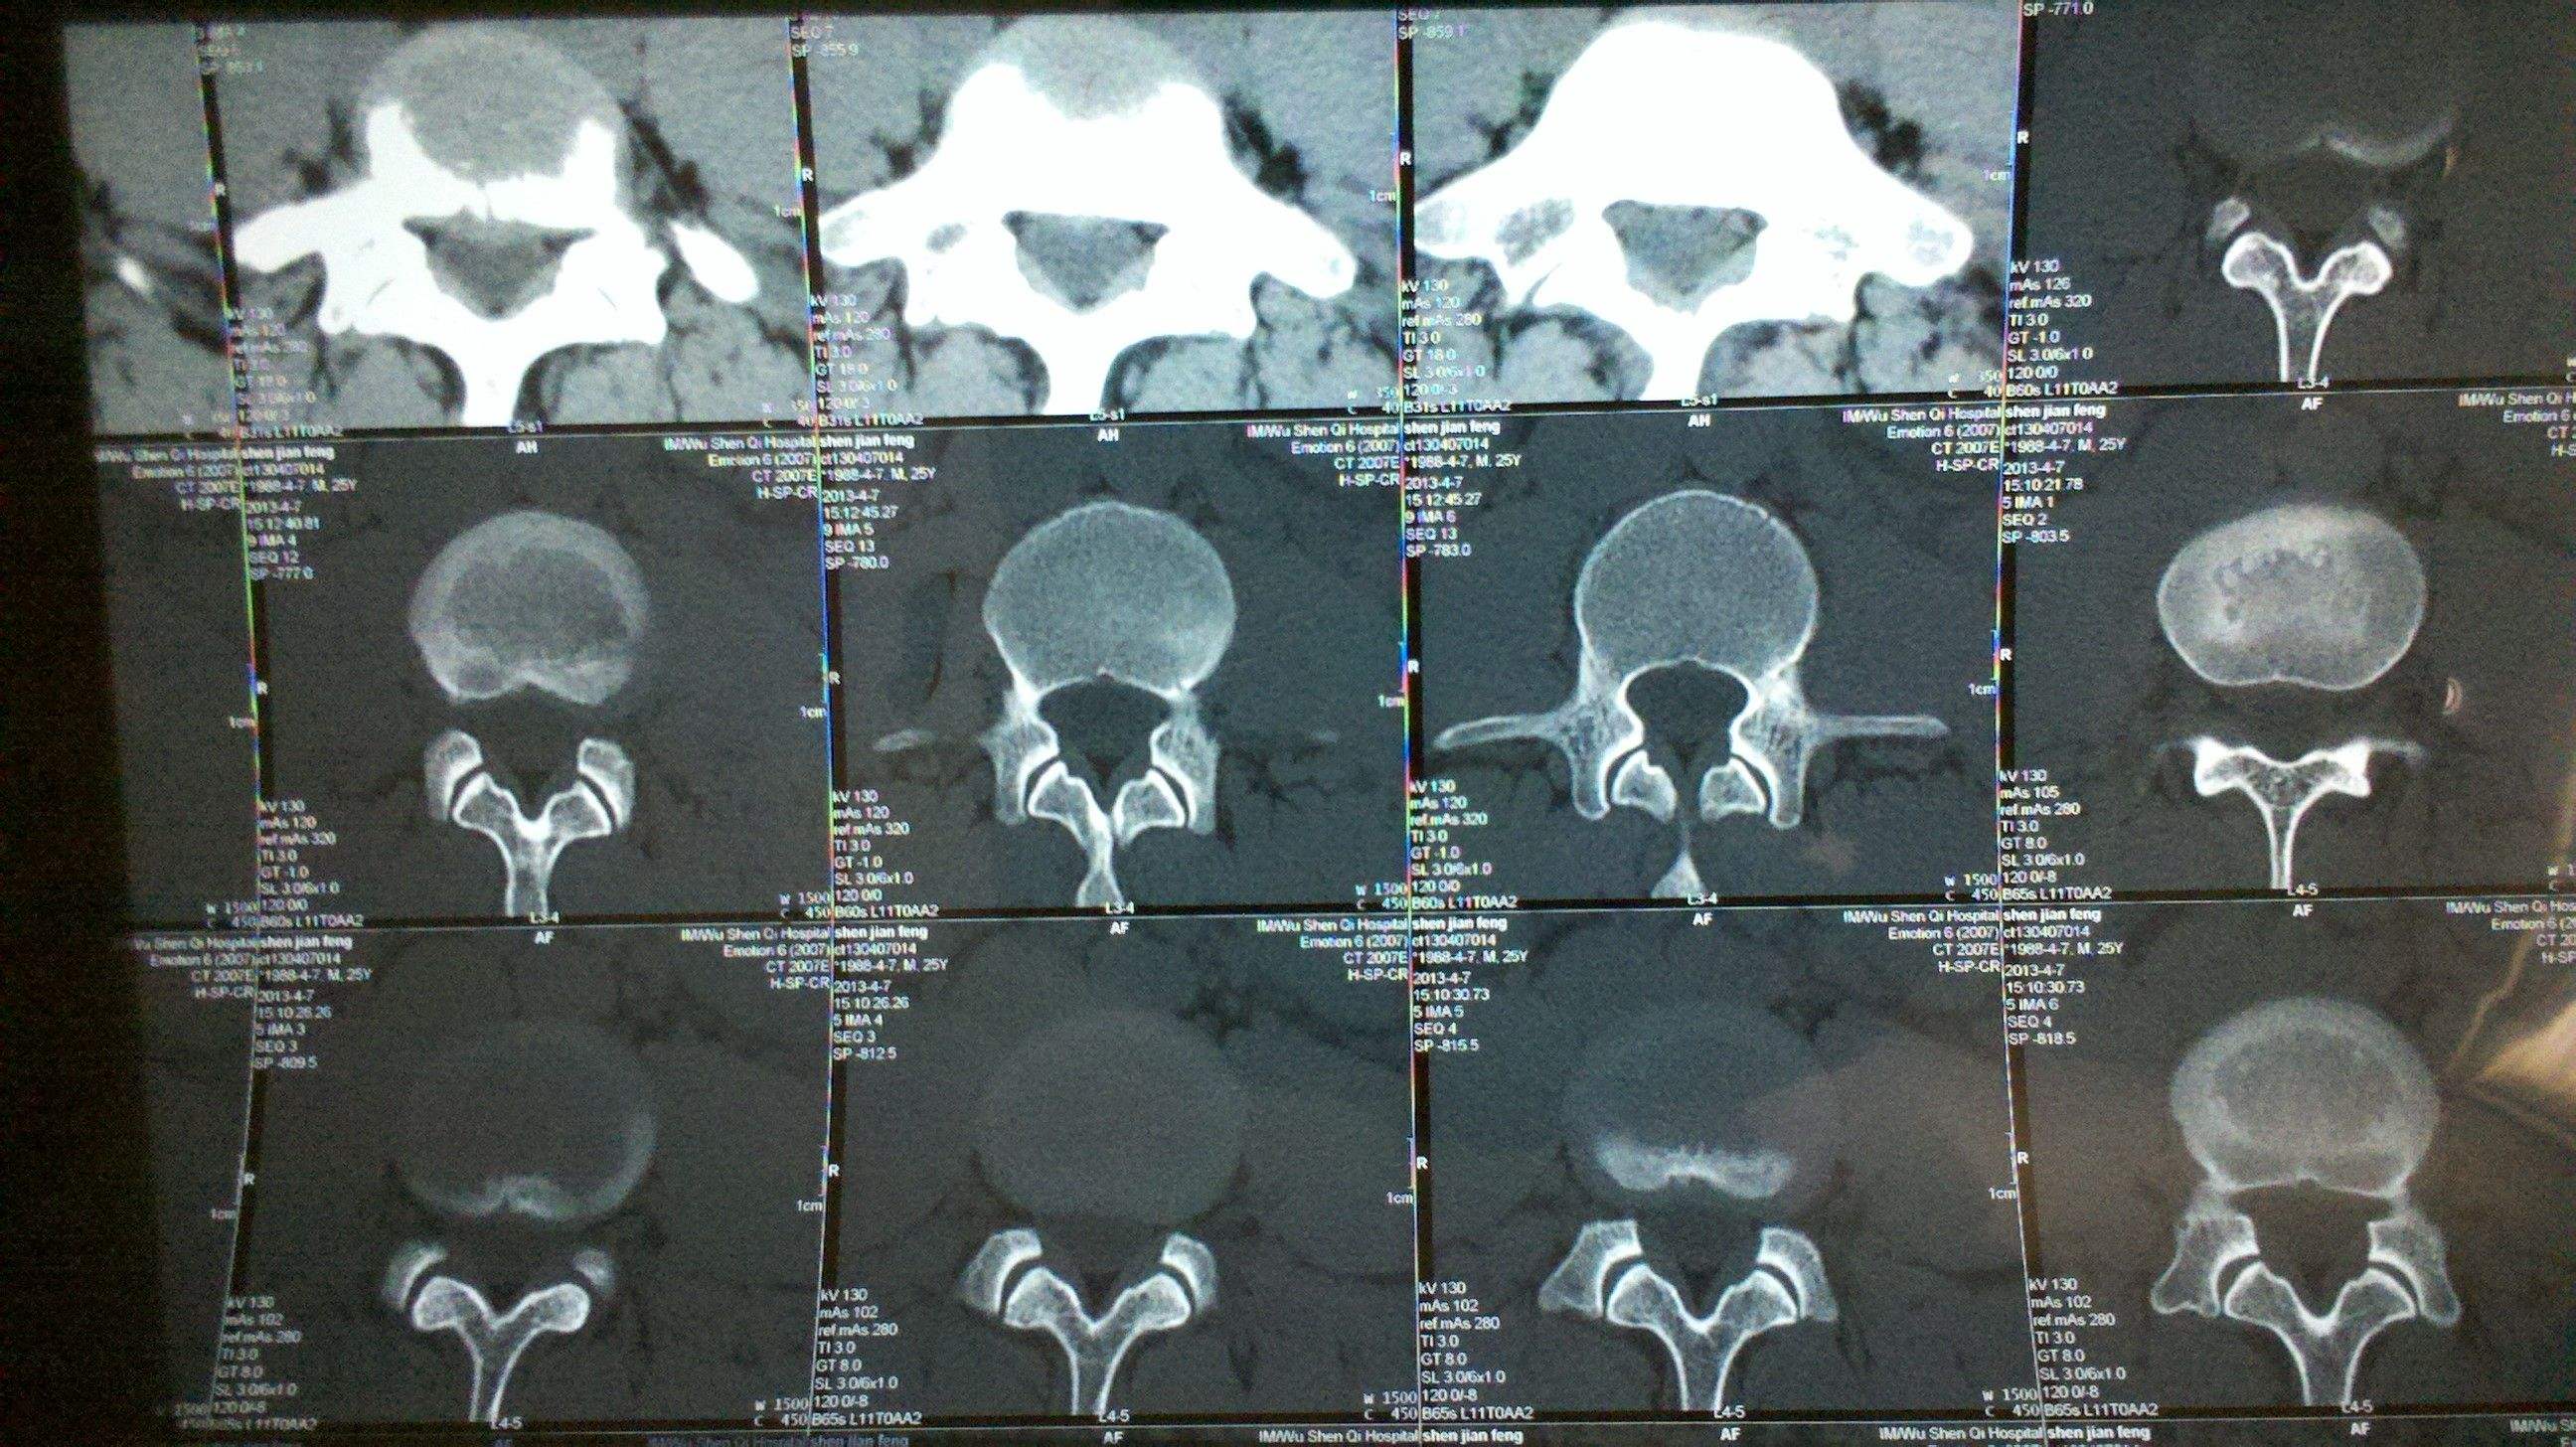

立即给阿姨约了一个腰椎CT,很快就排上了,结果拿回来一看,果真就是腰椎间盘突出症。可以在CT上看到明显的腰椎间盘突出以及局部的钙化压迫到了神经根,导致了现在的症状。

至于可以选择的辅助检查,建议腰椎CT就可以,当然,腰椎核磁MRI也是很好的选择,可以更清楚的看到脊髓和软组织的情况,具体检查方式的选择,还是要看医生的建议。